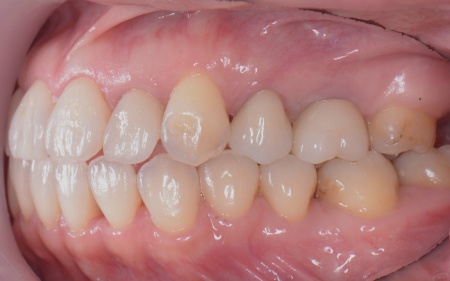

40代女性 矯正治療で噛み合わせを整えたあとセラミックの被せ物・詰め物で修復した症例

また、噛み合わせを確認したところ、奥歯で噛み合わせた際に上下の前歯が当たらず隙間ができる開咬(かいこう)が認められました。

開咬は前歯で食べ物を噛み切りにくくなるだけでなく、噛む力のバランスが崩れて奥歯に負担が集中しやすくなります。

修復治療が必要でしたがこの噛み合わせの問題を改善しないまま行うと、治療した歯に再び過度な力が加わって被せ物の破損・脱離や虫歯の再発を招くリスクが高まります。

まずは矯正治療を優先し、噛み合わせが整ってから虫歯の再発リスクの低いセラミックの被せ物・詰め物などで歯の形態と機能を回復する方針を提案し、同意いただきました。

最後に噛み合わせ全体のバランスを確認しながら新しく作製した被せ物や詰め物を装着し、見た目に問題がないか、噛み合わせが安定しているかを確認し、治療を終了しました。